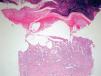

HistologíaSe obtuvieron 12 biopsias de pacientes con lesiones de EA inducidas por quimioterapia. Los hallazgos histológicos se resumen en la tabla 3.

La histología del EA por quimioterapia fue similar a la de las lesiones por citotoxicidad epidérmica de la quimioterapia. Encontramos una dermatitis de interfase con necrosis de queratinocitos en grado variable. Aparecieron así mismo alteraciones en la maduración de los queratinocitos

basales, y una asociación frecuente a siringometaplasia escamosa ecrina. A diferencia de otros cuadros de citotoxicidad epidérmica, el infiltrado inflamatorio fue muy escaso o ausente.

Existió una correlación clínico-patológica entre la intensidad de las lesiones del EA y la afectación histológica. Los pacientes con EPP grado 1 (G1) muestran tan sólo dilatación del plexo vascular superficial y afectación focal del estrato basal (fig. 5). Los pacientes con EPP G2 muestran dilatación del plexo vascular superficial, edema en dermis papilar, dermatitis de interfase con degeneración hidrópica basal y queratinocitos necróticos aislados (fig. 6). Los pacientes con EPP G3 muestran abundantes queratinocitos necróticos, intenso edema con despegamiento de la epidermis y dermatitis de interfase. En los casos con lesiones ampollares se produjo una necrosis completa del estrato epidérmico, con degeneración reticular de la dermis papilar (fig. 7).

En tres pacientes (25 % de las biopsias), encontramos cambios de siringometaplasia escamosa ecrina. Este hallazgo pudo verse tanto en biopsias de pacientes con afectación de grado 1 como de grados 2 y 3 (fig. 8).